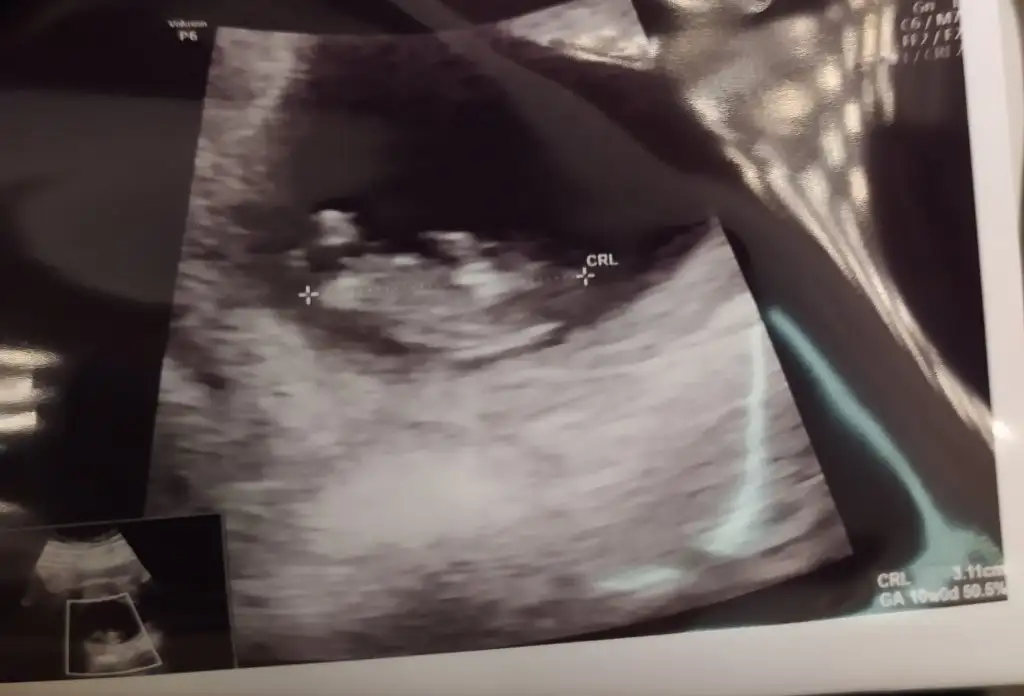

Kızlar ikili test konusunda konuşuluyor burda, benim de bu hafta karar vermem gerekiyordu.

Riskli çıkma durumunda ‘müdahale etme’ den kasıt bebeği aldırmak oluyor benim bildiğim yoksa herhangi bir operasyon ile bebeği düzeltme imkanı yok.

Gebeliğimi kolay elde etmedim; inancım gereği de böyle bir şeyi hiç düşünmem sanırım